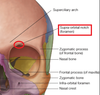

Where is the Supraorbital foramen/notch?

What structures can be found there

the supraorbital nerve and vessels are located here.

Where is the infraorbital foramen/notch?

What structures are found here?

the infraoribal nerve and vessels are found here.

Where are the infra and supratrochlear foramen located?

What structures are found here?

supratrochlear nerve and vessels, as well as infratrochlear nerve and vessels.

Where is the zygomaticofacial foramen?

what is located here?

zygomaticofacial nerves and vessels.